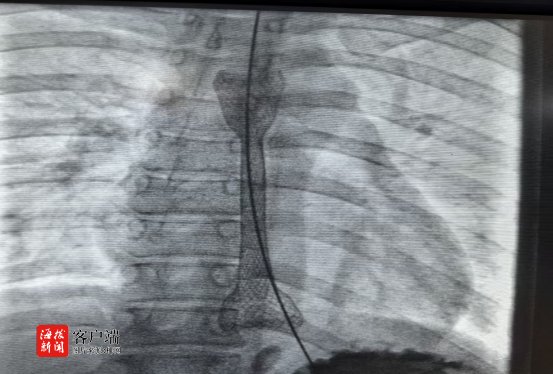

4月16日,由消化内科蔡笃雄主任医师、高飞主治医师,介入血管外科孙刚副主任医师、廖勇主治医师,介入导管室林子义技师、谢春花副主任护师等组成的精锐手术团队严阵以待。内镜下,食管狭窄处仅露出一条细小缝隙,手术难度极高。但在X射线透视的精准引导下,手术团队凭借丰富经验和高超技艺,经过多次尝试,终于让导丝成功穿过狭窄段进入胃腔!随后,5mm和8mm扩张球囊逐级撑开狭窄食管,最后顺利置入食道金属支架。造影剂顺利通过食管狭窄段进入胃腔,此次高难度手术取得良好效果。